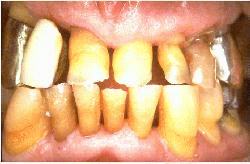

El mismo paciente después del tratamiento, la patología periodontal se ha eliminado y las profundidades de bolsa son de 1-2 mm.  La condición periodontal se observó durante tres citas en un mes. La salud periodontal se mantuvo por los procedimientos de higiene oral y la rehabilitación protética del maxilar superior.